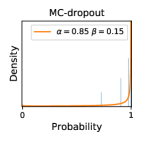

To model how different classifiers will respond to a given input , we assume that the prediction from classifier is sampled from a beta distribution that is characterized by two parameters by and . We further assume that is fixed to the same constant value for all ’s. Under this assumption, each input can be described by ( can be calculated since is fixed), easing further analysis. The Severity Level (SL) of the case represented by image can be characterized by the parameter . The larger the value of , the more severe the case of is. When and are close, the case is ambiguous as the distribution shifts towards being symmetric (i.e. signifying much disagreement among classifiers) rather than being one-sided (i.e. consensus among classifiers that is negative or positive). We provide a set of examples in Figure 2 and also Figure S.8 in the supplementary materials showing how the beta distribution can be used to capture diverse predictions given by an ensemble learner.

Three types of ensemble methods (stacking ensemble, MC-dropout and TTA) described in Section 3.1 were evaluated in our experiments. We did not adopt the deep ensemble approach [1] in our case study because we did not manage to train the networks from scratch (random initialization). Our solution was to train all the models by reusing the weights from a pretrained ImageNet model, which proved to work well but also prevented us from implementing the original deep ensemble approach [1].

In contrast, the MC-dropout method showed the worst overall performance among the three, as it can be seen from the high ratios of SL0 examples among the uncertain negatives in Figure 4. The histograms in Figure 2 provides another perspective to look into the phenomenon, where a decent proportion of MC-dropout model’s predictions on SL0 inputs entailed low confidence (far from 0 or 1), which from another angle explained why MC-dropout was less specific in terms of lower FNP; many no-DR inputs (i.e. SL0) were erroneously assigned high uncertainty by MC-dropout models.

It is still an open question why the evaluated MC-dropout networks signaled relatively high uncertainty on SL0 & SL3 & SL4 data that are less likely to be ambiguous. We conjecture that much of the “uncertainty” indicated by disagreement among test-time dropout samples actually reflects the stochastic nature of dropout networks rather than the real decision uncertainty associated with the data. It is worth noting that the MC-dropout model we evaluated was not weak per se; they all achieved above Area Under Curve (AUC) scores on test sets. The weakness of individual test-time samples (which explains their low-confidence predictions on SL0 & SL3 & SL4) might have been hidden when they are aggregated into an ensemble—a well-known advantage of ensemble learning. Our results suggested that the uncertainty information given by implicit ensemble methods such as MC-dropout and TTA might not be as reliable as that from explicit ensemble approaches (e.g., stacking ensembles). Similar findings on MC-dropout can be found in some previous papers [1].